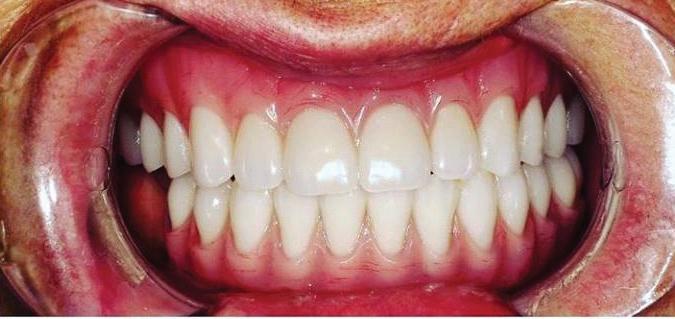

Face The Future

Can just four implants replace all of the teeth on the top or the bottom of your mouth? Thanks to advances in dental implant technology, that answer is a resounding yes.

Tooth loss is extremely common among adults, especially as we age. Rather than living with the discomfort and hassles of dentures, many people are opting for what is called “all-onfour” dental implant restoration.

An implant is a small titanium screw

that fits inside your jawbone and replaces the root-part of a missing tooth. Minor surgery is required to insert the implants. Once the implant is in place, a crown is attached to give you a highly realisticlooking and functional prosthetic tooth. You do not need a dental implant for each and every one of your missing teeth. All you need is four precisely placed implants on the top of your mouth, and four on the bottom, to restore your full smile. That’s the beauty of the all-on-four. And because the implant is made of titanium, it has the unique ability to fuse to living bone and function as part of it. So eventually, the dental implant becomes part of the jawbone and serves as a strong, long-lasting foundation for your new teeth.

Besides ensuring that your implants are permanently fixed in place, this bone fusion has another important benefit: it prevents future bone loss in the jaw. This helps to maintain a more youthful facial structure – and better oral health. But perhaps the biggest

Please see “All-On-Four,” page 61

301-805-6805 page 16 | Your HEALTH Magazine Since 1977, AT HOME CARE, INC. has helped thousands of persons enjoy the pleasure and peace of staying at home. Your Care. Your Way. Our Services are designed to make life safer and more enjoyable: • Personal care and hygiene • Meal Preparation • Shopping • Light Housekeeping • Laundry • Activity and Appointment Assistance • Companionship • Medication Reminders • Exercise assistance Call today to discuss your personal situation. 301-421-0200 Visit us online at AtHomeCareInc.com All-On-4: Same Day Smiles CALL TODAY TO GET YOUR OLD SMILE BACK! 301.294.8700 Dental Implant Center of Rockville 77 South Washington Street, Suite #205 Rockville, MD 20850 • www.DrSreeni.com Courtesy 3D Planning For Implants When patients bring a 3D scan with them to or have one taken in the office. Appointment needs to be scheduled before July 15, 2024 Missing Teeth or Tired of Wearing Dentures? Thanks to advances in dental implant technology, just four implants can replace all of the teeth on the top or the bottom of your mouth. All-On-Four Dental

Implants